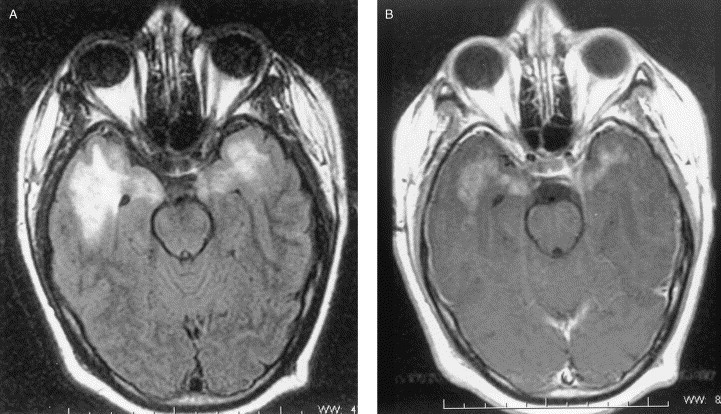

Stroke Syndrome:

“Dejerine and Roussy” Syndrome - Thalamic (on this case on the right). Infarction of sensory relay nucli due to occlusion of thalamogeniculates. These come from the PCA